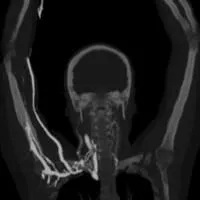

MR venography (MRV) can be performed in two ways. First is direct MRV. The physician injects contrast into a small arm vein. Shortly thereafter, the MRI scanner creates images as the contrast passes through the arm and chest. Direct MRV shows only veins, and only in one arm. In contrast is indirect MRV. Again, the physician injects contrast into a small arm vein. In contrast to direct MRV, scanning begins after a delay. First, injected contrast travels through the heart, the lungs, the arms, and returns through the arm veins. At this time, the MRI scanner creates images, showing both arteries and veins, in both arms. MRV shows the veins while eliminating other structures. MRV requires no radiation. If used in conjunction with MRI, superb soft tissue detail is available. Excellent depiction of fibrous bands, muscle anomalies, bones, and brachial plexus is possible with the combination of MRV and MRI.

This patient had an MR angiogram, followed by an MR venogram. Slide the handle side to side to see the difference between the two studies.